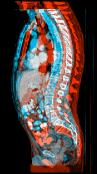

In order to investigate the performance of our method on high-resolution 3D data, we measured the average runtime over 986 registrations on a dataset of follow-up thorax abdomen CT scans provided by the Radboud University Medical Center, Nijmegen, Netherlands. The images have resolutions in the range of . As full image resolution was slightly out of reach due to memory restrictions of the GPU, we evaluated our approach on half, quarter, eighth and sixteenth resolution per dimension.

For the highest resolution, average runtime was seconds, with an average speedup of compared to the CPU-based parallel OMP implementation (Table 1). On the lower resolutions, our method achieves sub-second runtimes at a speedup of about one order of magnitude. A majority of the runtime on the lower resolutions is spent on the multi-level creation, due to the large memory transfer and downsampling.

It is prudent to ask whether moving from double precision to single precision on the GPU introduces differences due to rounding. In fact, we observed that this can have an effect (Figure 1). However, it typically only occurs when there are no clear correspondences, such as in regions of the colon with different content, or when the examination table is visible in one of the two scans. In these areas, there is no strong objective function gradient in either direction during optimization, so that numerical differences have a larger impact. However, we argue that if such areas were to be registered accurately, a more elaborate model that accounts for the possible removal of structures would have to be employed in any case.